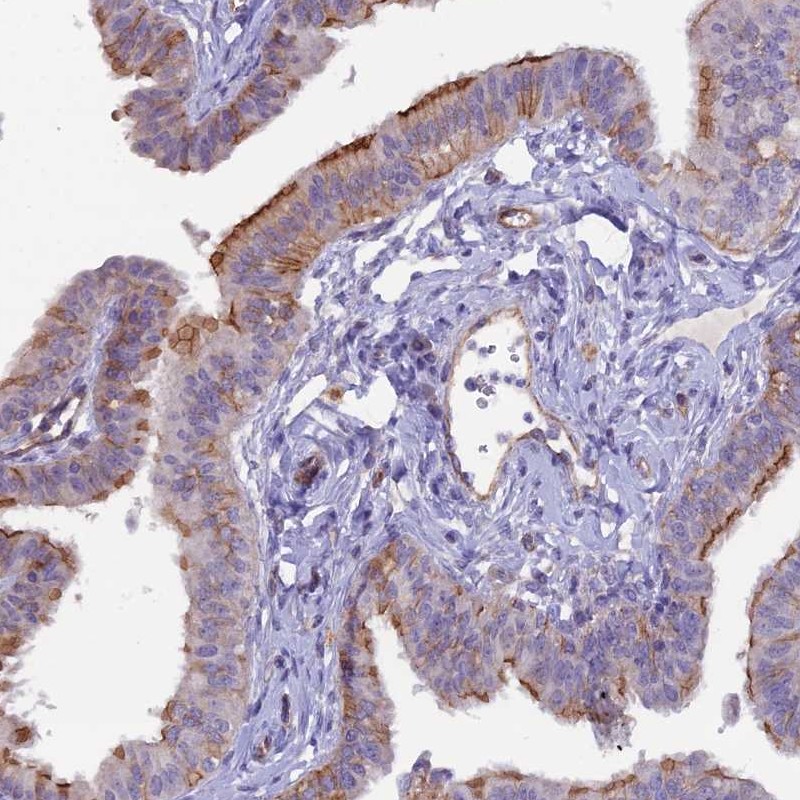

Immunohistochemical staining of human fallopian tube shows strong membranous positivity in ciliated cells.